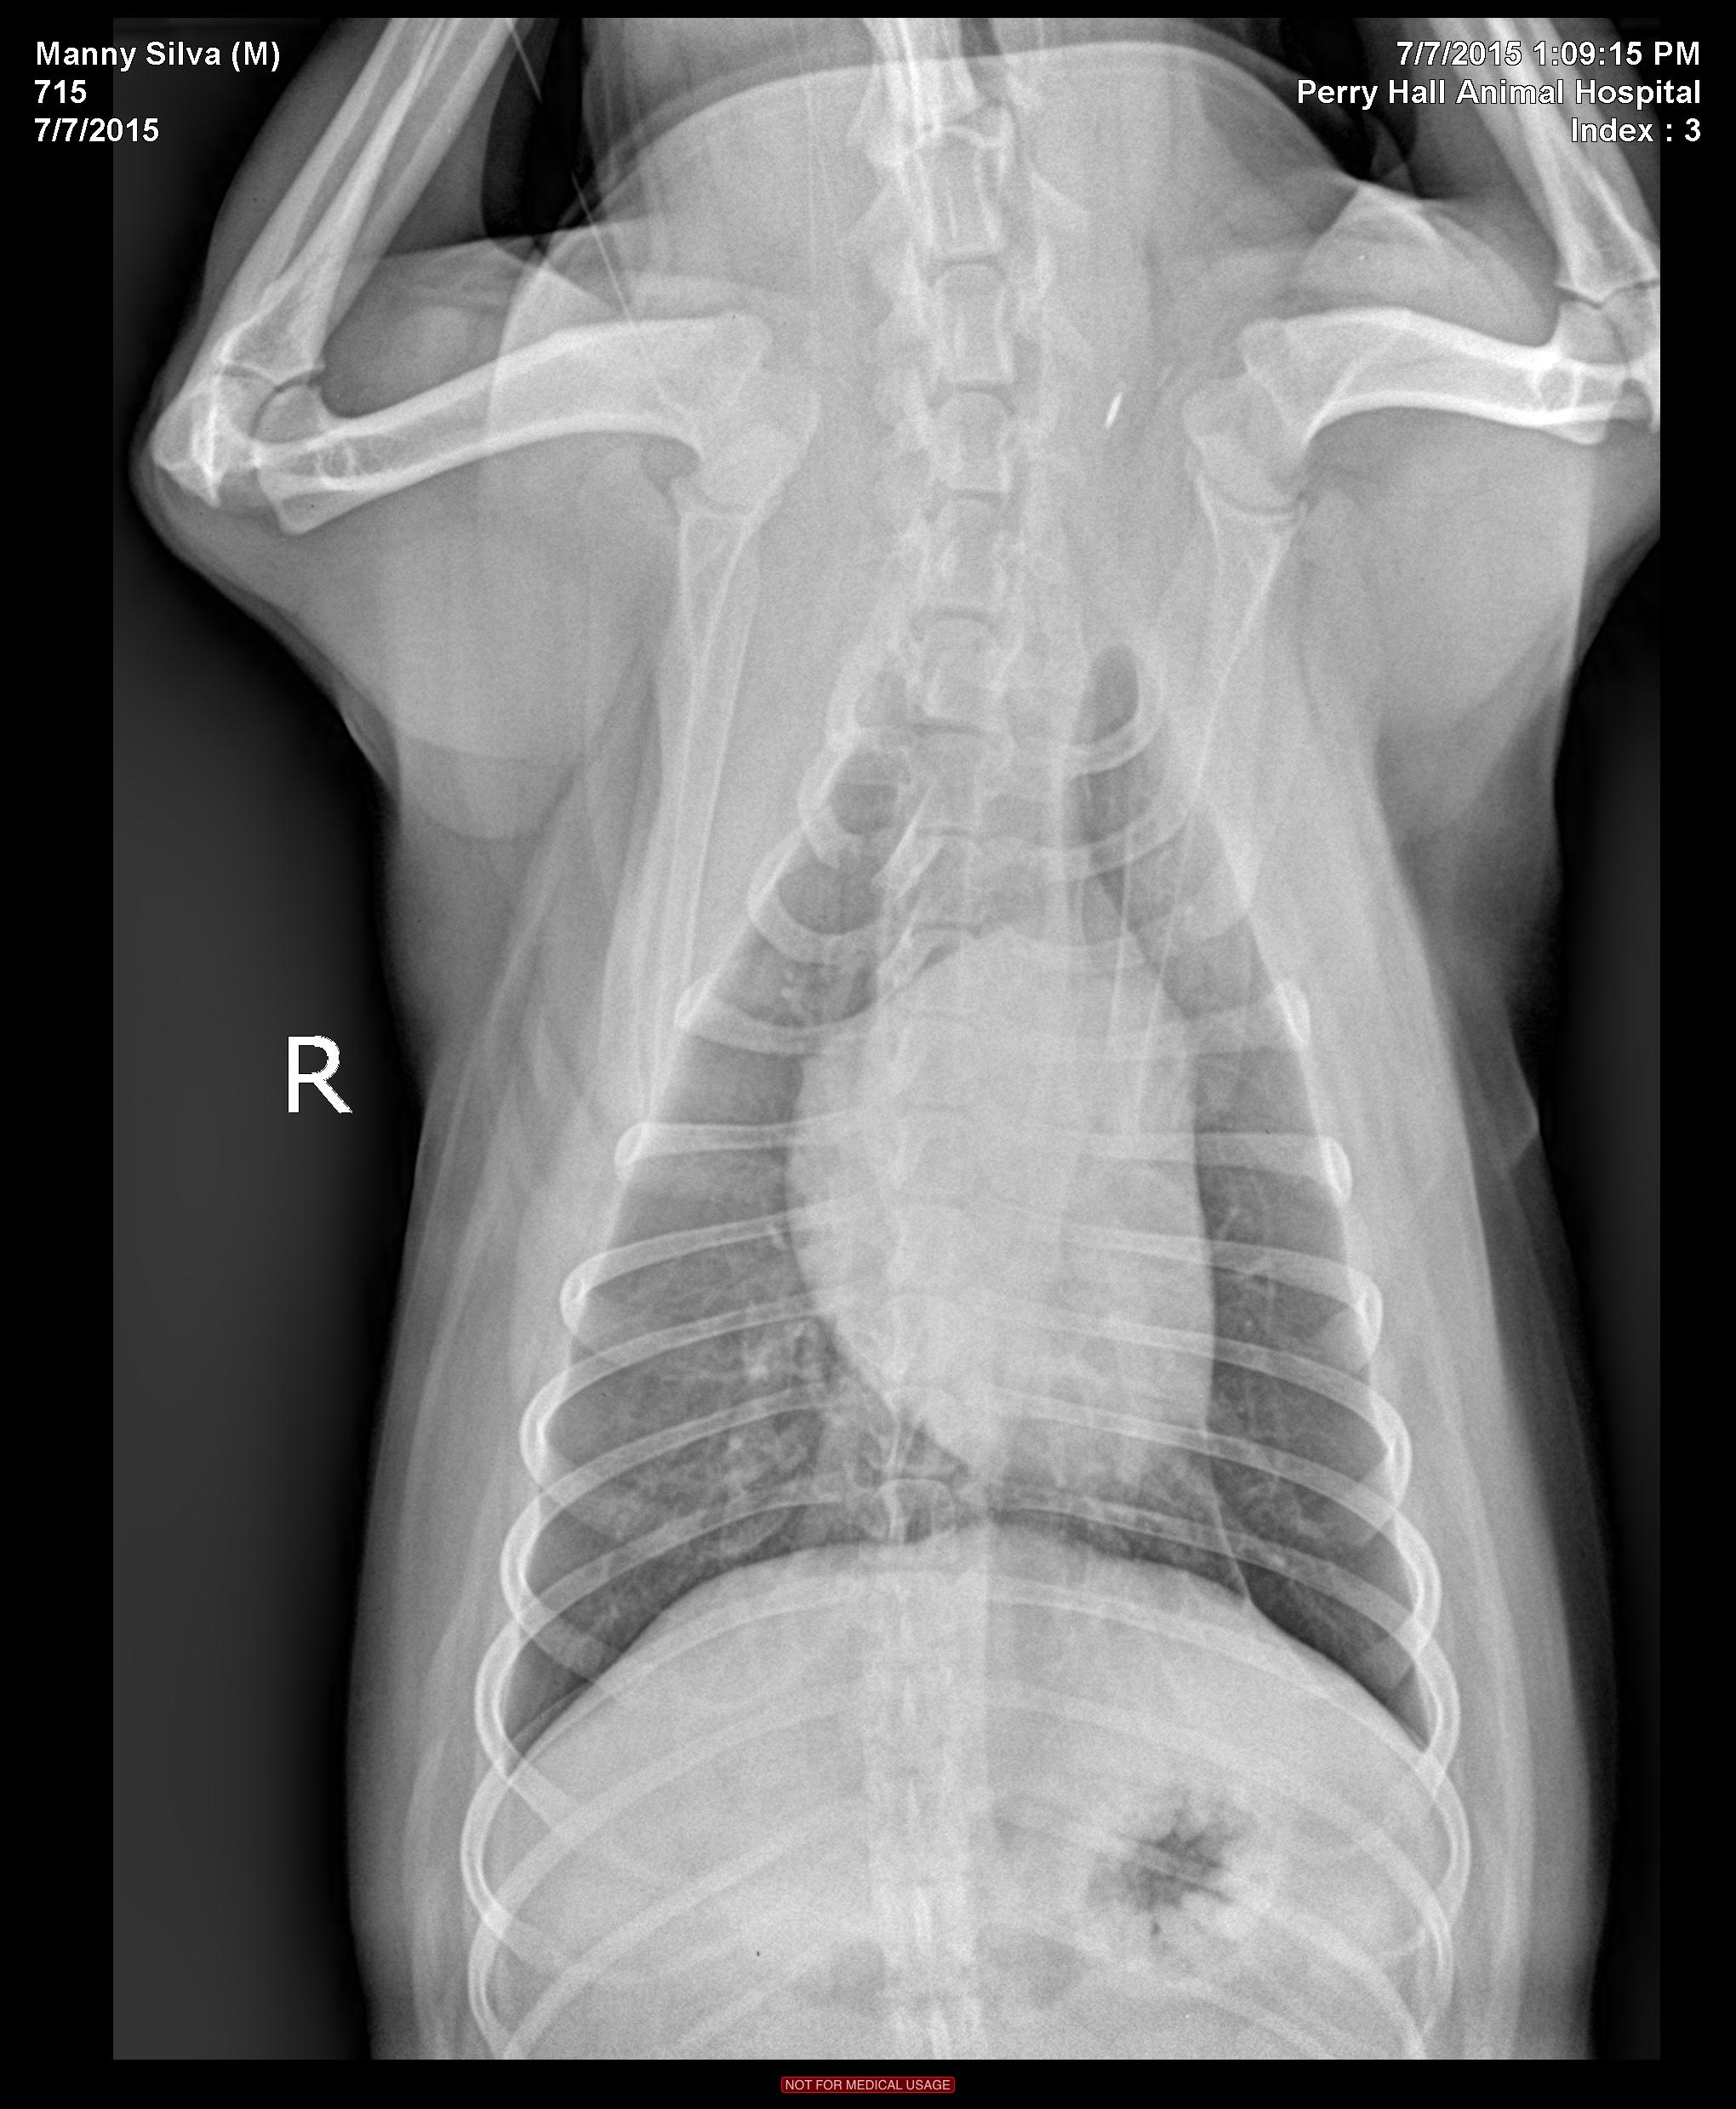

History of 3 recent episodes of hairball-type cough/wheeze/gag. Physical exam showed all WNL; no coughing episodes during the exam or during the stress of radiographs. CBC and chemistry panel pending at this time.